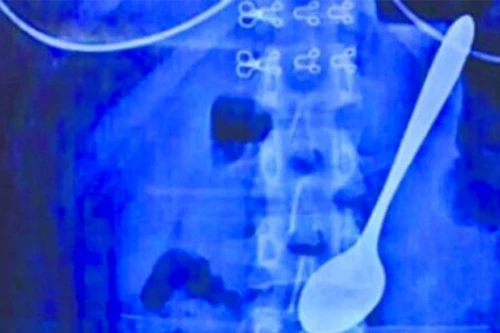

Bị giật mình, nuốt luôn thìa kim loại